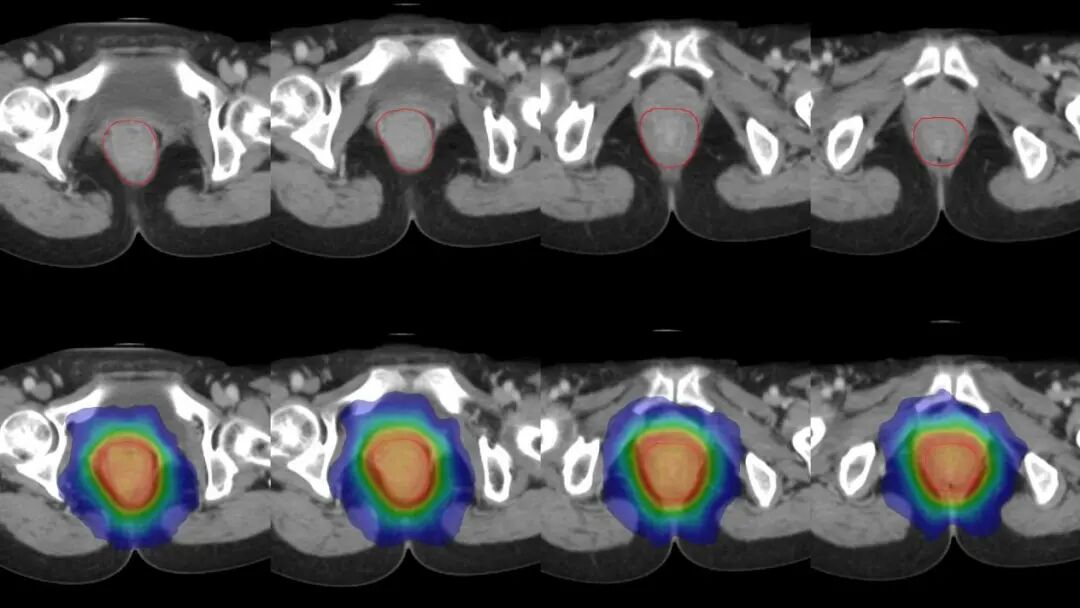

图注:上图红线为根据磁共振勾画的肿瘤靶区。下图为放射剂量分布,可见射线分布集中于肿瘤病灶,中心区高剂量照射,周边剂量快速跌落,形成锐利的集束聚焦照射,周围组织得到良好保护。